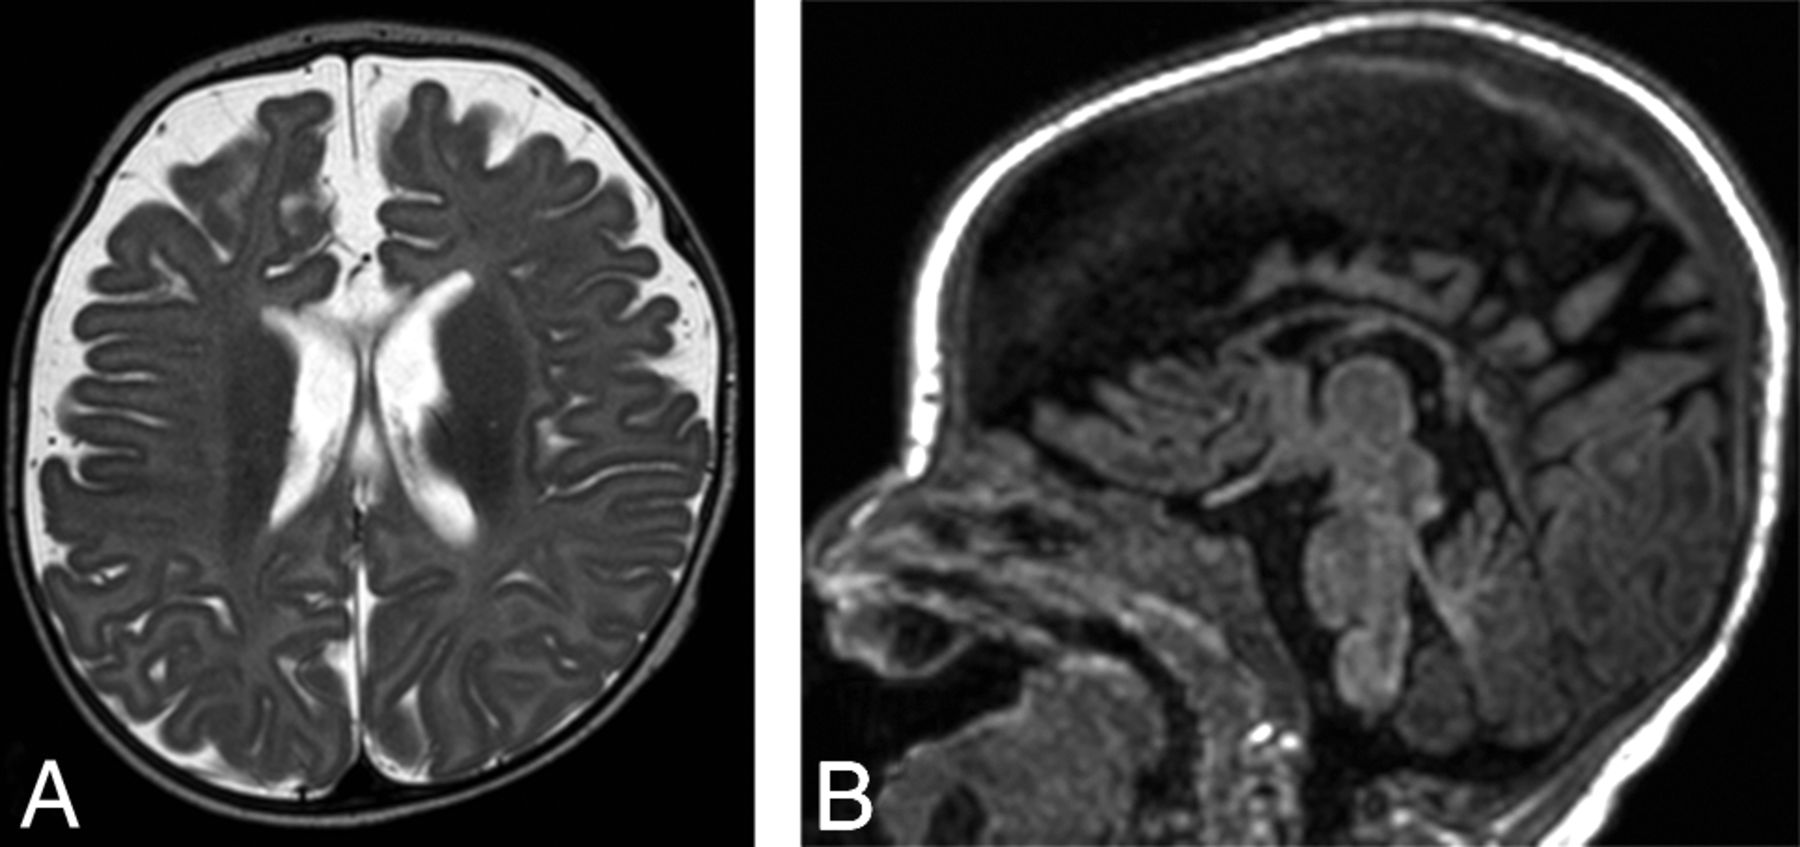

Axial T2-weighted image (A) and sagittal T1-weighted image (B) obtained in patient 1 approximately 3 months after acute HPeV infection show new diffuse enlargement of the extra-axial spaces and thinning of the corpus callosum, suggesting volume loss.